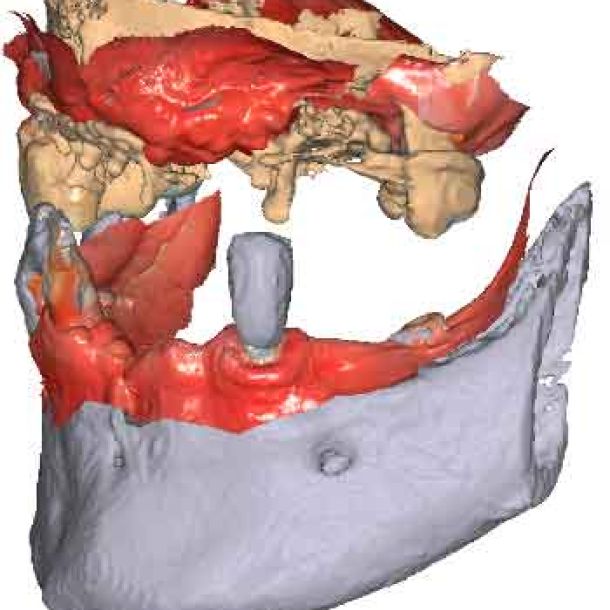

3D models - Bite scan from intra-oral scanner

Step 2 – CBCT acquisition

When traditional IOS scans lack necessary references, Cone Beam Computed Tomography (CBCT) data serves as a possible alternative. By utilizing CBCT scans, clinicians can establish accurate reference positions for treatment planning.

To be able to use CBCT data as initial models, we need to transform the DICOM file into an STL file.